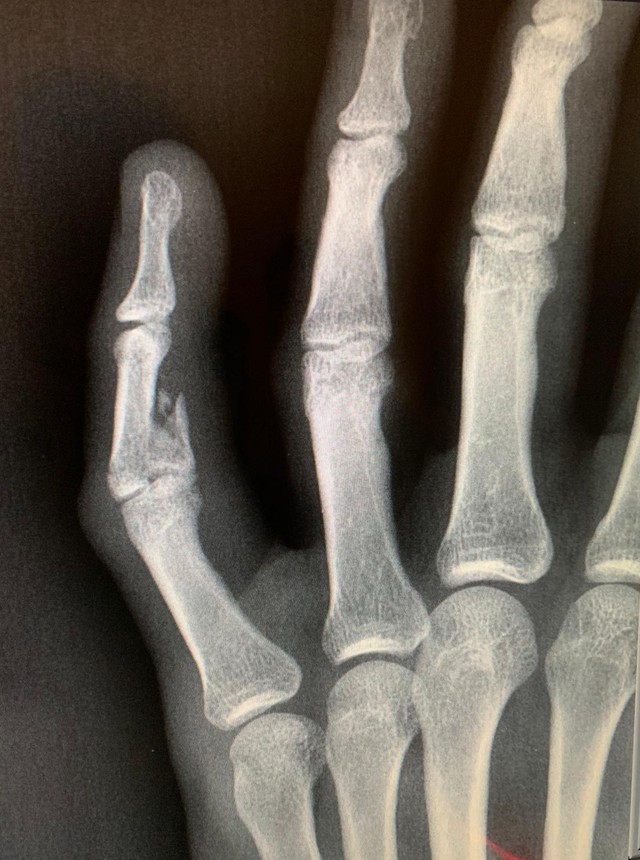

O Vasco terá Guarín contra o Goiás. Preservado contra o Volta Redonda por conta de dores musculares, o colombiano participou normalmente do treino desta terça-feira e vai para o jogo, quinta, pela Copa do Brasil. Mesmo com mão direita imobilizada, por conta de uma fratura no dedo mínimo diante do ABC.